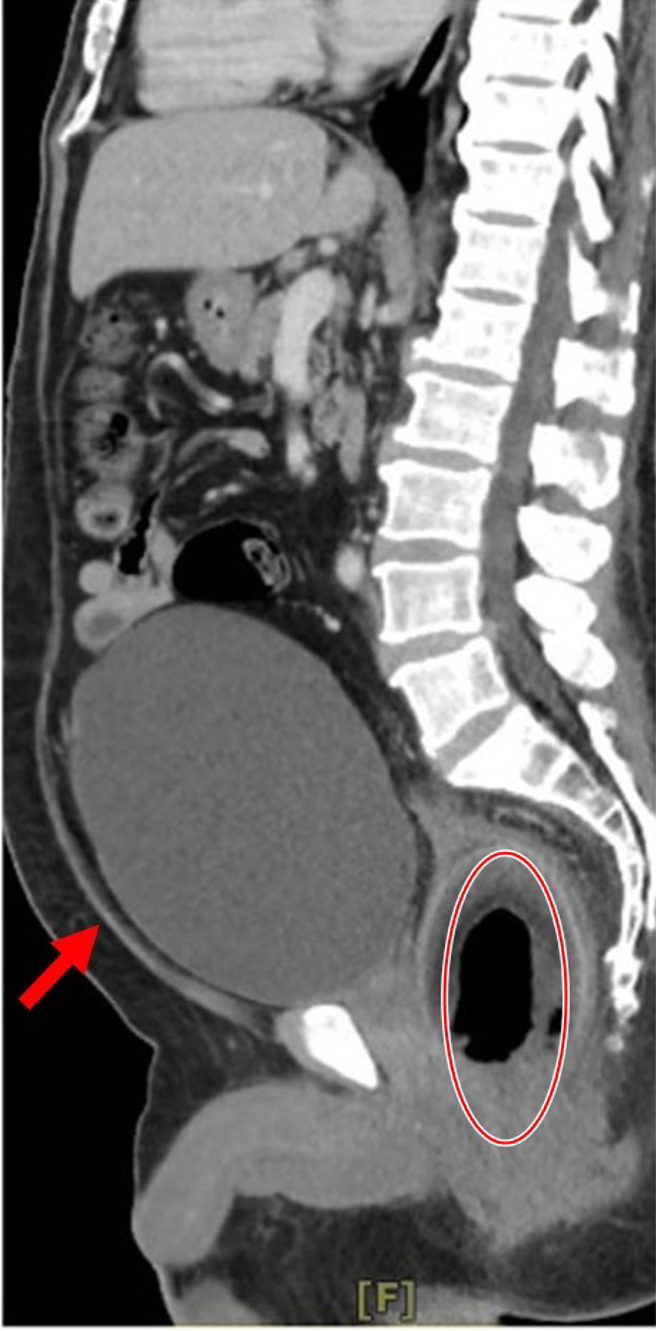

电脑断层检查影像中,可看到男子直肠内有一颗椰子(红圈处),堵住了膀胱的开口(红箭头处),导致膀胱涨尿到近2000C.C.,如一颗橄榄球,险些涨破。(图/陈致一医师提供)